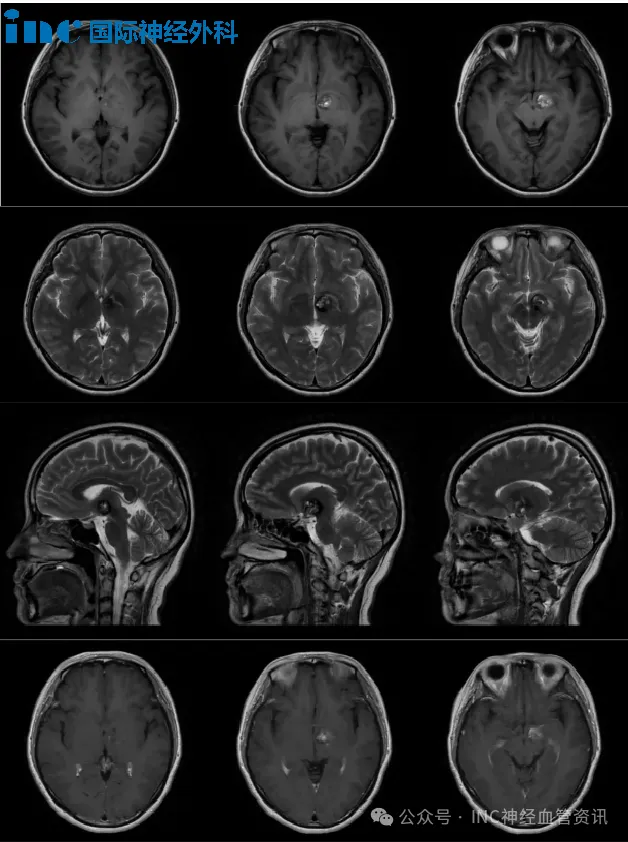

术前MRI

“每次出血都如同经历一次生死考验,我们不敢想象下一次发作的后果——是否会出现偏瘫?能否保留语言功能?”文文与家人陷入困境:保守治疗无法阻止病情进展,而手术又被评估为高风险,是否只能被动等待病灶再次出血?